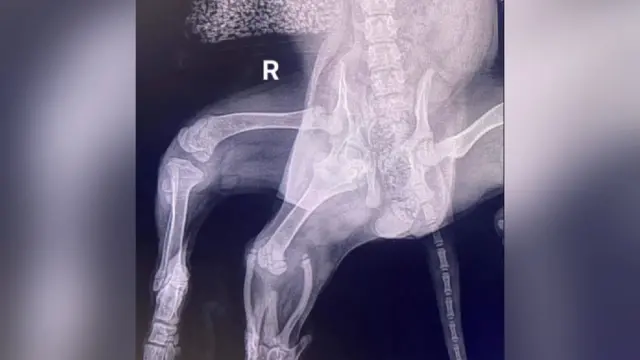

ఏరియల్, ఆరు కాళ్లతో పుట్టిన కుక్క ఇది. ఒక సూపర్ మార్కెట్ కారు పార్కిగ్లో దీన్ని చూశారు. ఈ కుక్కకు ఉన్న అదనపు కాళ్లను తొలగించేందుకు శస్త్రచికిత్స చేశారు.

‘‘ఏరియల్ను మొదట పరీక్షించిన వైద్యుడు దానికి అదనంగా రెండు వెనుక కాళ్లతో పాటు అదనపు వల్వా (జననేంద్రియం)కూడా ఉందని చెప్పారు’’ అని 42 ఏళ్ల మికీ వెల్లడించారు.

‘‘ఒకే వైపుకు రెండు తుంటి కీళ్లు ఉండటం వల్ల దానికి కటి (పెల్విస్) భాగం పూర్తిగా ఏర్పడలేదు. ఫలితంగా వెనుకవైపు కుడికాలుకు ఎలాంటి కండ లేదు. కాబట్టి దాన్ని కూడా తొలిగించాల్సి వస్తుందని అనుకున్నారు. ఇటీవలి కాలంలో ఆ కాలు కాస్త బలంగా మారడంతో దాన్ని తొలిగించాల్సిన అవసరం రాలేదు’’ అని ఆయన వివరించారు.